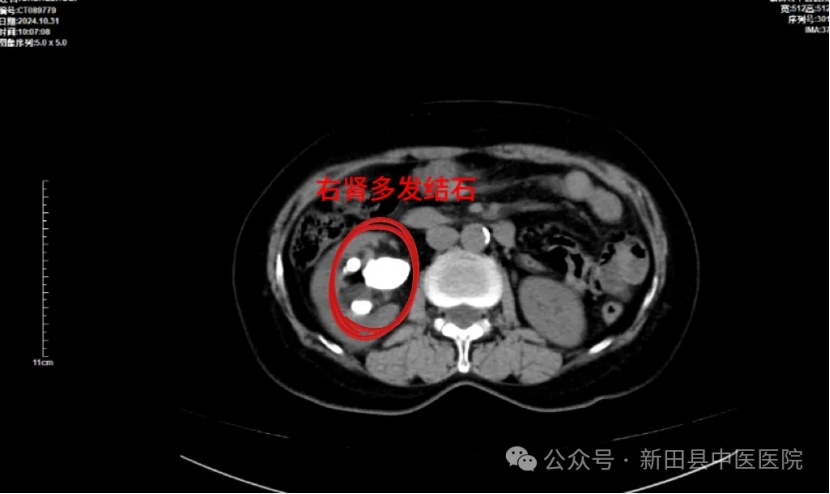

病例分享2

病例:患者单女士,59岁,因体检时发现右肾结石10余天入院。查体:双肾区无明显叩击痛,双侧输尿管行程区及膀胱区无压痛。CT提示右肾多发结石,肾盂内铸型结石,肾盂及右肾盏稍积水扩张,左肾小结石。

▲术前CT

治疗:患者右肾多发结石,最大结石约35x30mm,右肾轻度积水,于2024年11月4日在全麻下行右侧PCNL术,术后予抗感染、解痉止痛、补液等对症支持治疗。